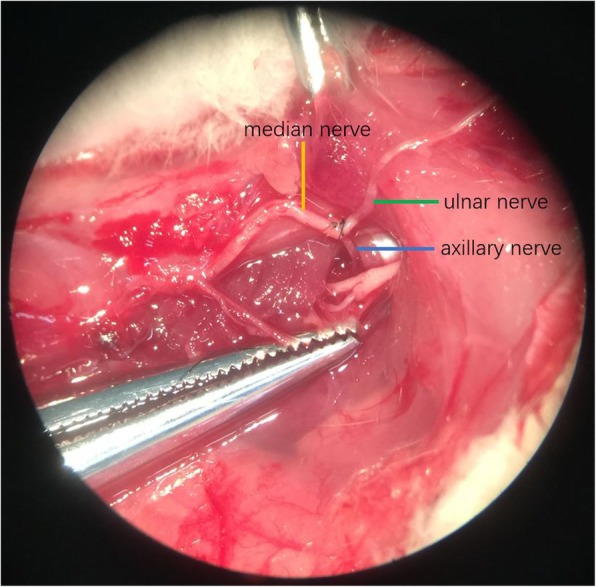

Group C (cC7 --- median and axillary nerves): A Z shape incision was made to expose the ulnar nerve, median nerve and axillary nerve in the right axilla. The axillary nerve was cut off at the quadrilateral foramen. The ulnar and median nerves were separated to enough length for suture in the axilla. Then they were cut off. The proximal end of ulnar nerve was sutured to the distal ends of the axillary and median nerves without tension. (Fig. 3).

Fig. 3.

cC7 transfer to median and axillary nerves: Axillary nerve and median nerve were separated to enough length for suturing to the ulnar nerve without tension

In the experiment, the nerves were sutured with 11–0 nylon (Ethicon, Johnson & Johnson, New Brunswick, New Jersey) under 10 times microscope.